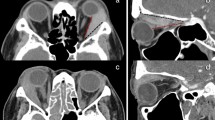

Representative HRCT images with ground-glass attenuation suggestive of lymphatic congestion and MFF. (A, B): A 53-year-old female with S-LAM. She was diagnosed as having LAM histopathologically at the age of 45 when she had a right pneumothorax. Subsequently, ground- glass attenuation was noted in the right upper lobe (A) which ameliorated spontaneously 3 months later (B). (C,D) A 48-year-old female with S-LAM. HRCT revealed a small number of cysts in lung parenchyma in which focal ground-glass attenuation and the thickening of interlobar septa were noted (C). These findings were suggestive of lymphatic congestion which exacerbated 3 months later (D). Lung biopsy confirmed the diagnosis of LAM. (E,F) Representative images of lymphatic congestion in the mediastinum. This patient was a 56-year-old female with S-LAM whose diagnosis was established histopathologically by biopsy of retroperitoneal tumors. HRCT images showed the pathognomonic cystic appearance with some large cysts due to advanced LAM disease. Note the mediastinal widening, especially of the area dorsal to the trachea (E). The image obtained with intravenous contrast material delineated low attenuated areas surrounded by soft tissue attenuation, suggesting the cystic dilatation of mediastinal lymphatics and/or cystic enlargement of the mediastinal lymph nodes (F). She had initiated a fat-restricted diet as sirolimus had not yet been approved. However, these mediastinal lesions had successfully shrunk while being on the fat-restricted diet. (G,H) A 63-year-old female with S-LAM. HRCT images showed MFF as focal low-attenuation areas in both the interatrial (arrowheads) and interventricular (arrows) septums, on both unenhanced (G) and enhanced (H) images.

A representative S-LAM patient with MFF, but neither MMPH nor sclerotic bone nodules is shown in Fig. 4G,H. She had a spontaneous pneumothorax at the age of 41 and had undergone VATS for the treatment of pneumothorax. Pathological examination failed to discover LAM as the underlying disease which caused pneumothorax at that time. However, we re-evaluated the lung specimen archive when she was referred to our hospital due to a pneumothorax recurrence at the age of 63, and confirmed that she had LAM. Her HRCT revealed the typical cystic appearance with a right pneumothorax (not shown). In addition, MFF as a focal low attenuation area in the interatrial septum was observed on both unenhanced (Fig. 4G) and enhanced (Fig. 4H) images.